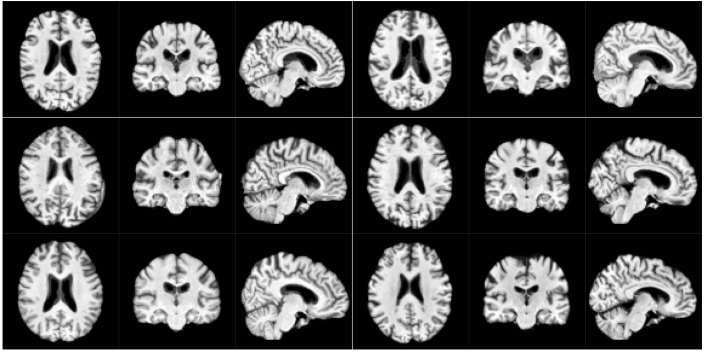

Qualitative analysis of the compared methods reveals that samples from VAE are not anatomically correct in many cases and display regions that appear scrambled. WGAN generates anatomically viable samples, however in many of them the cortical folds do not follow the anatomical structure. Additionally, as in VAE, samples exhibit regions where artifacts are dramatically different from the rest of the volume. Samples from our model are the most anatomically correct due to starting from the fixed template. However, the samples occasionally have a wavy visual quality due to improperly generated random deformation fields at finer scales. We furthermore observe a lack of sufficient topological diversity in the cortical folds. Samples for each of the above methods are shown in Section A of Supplementary Material.